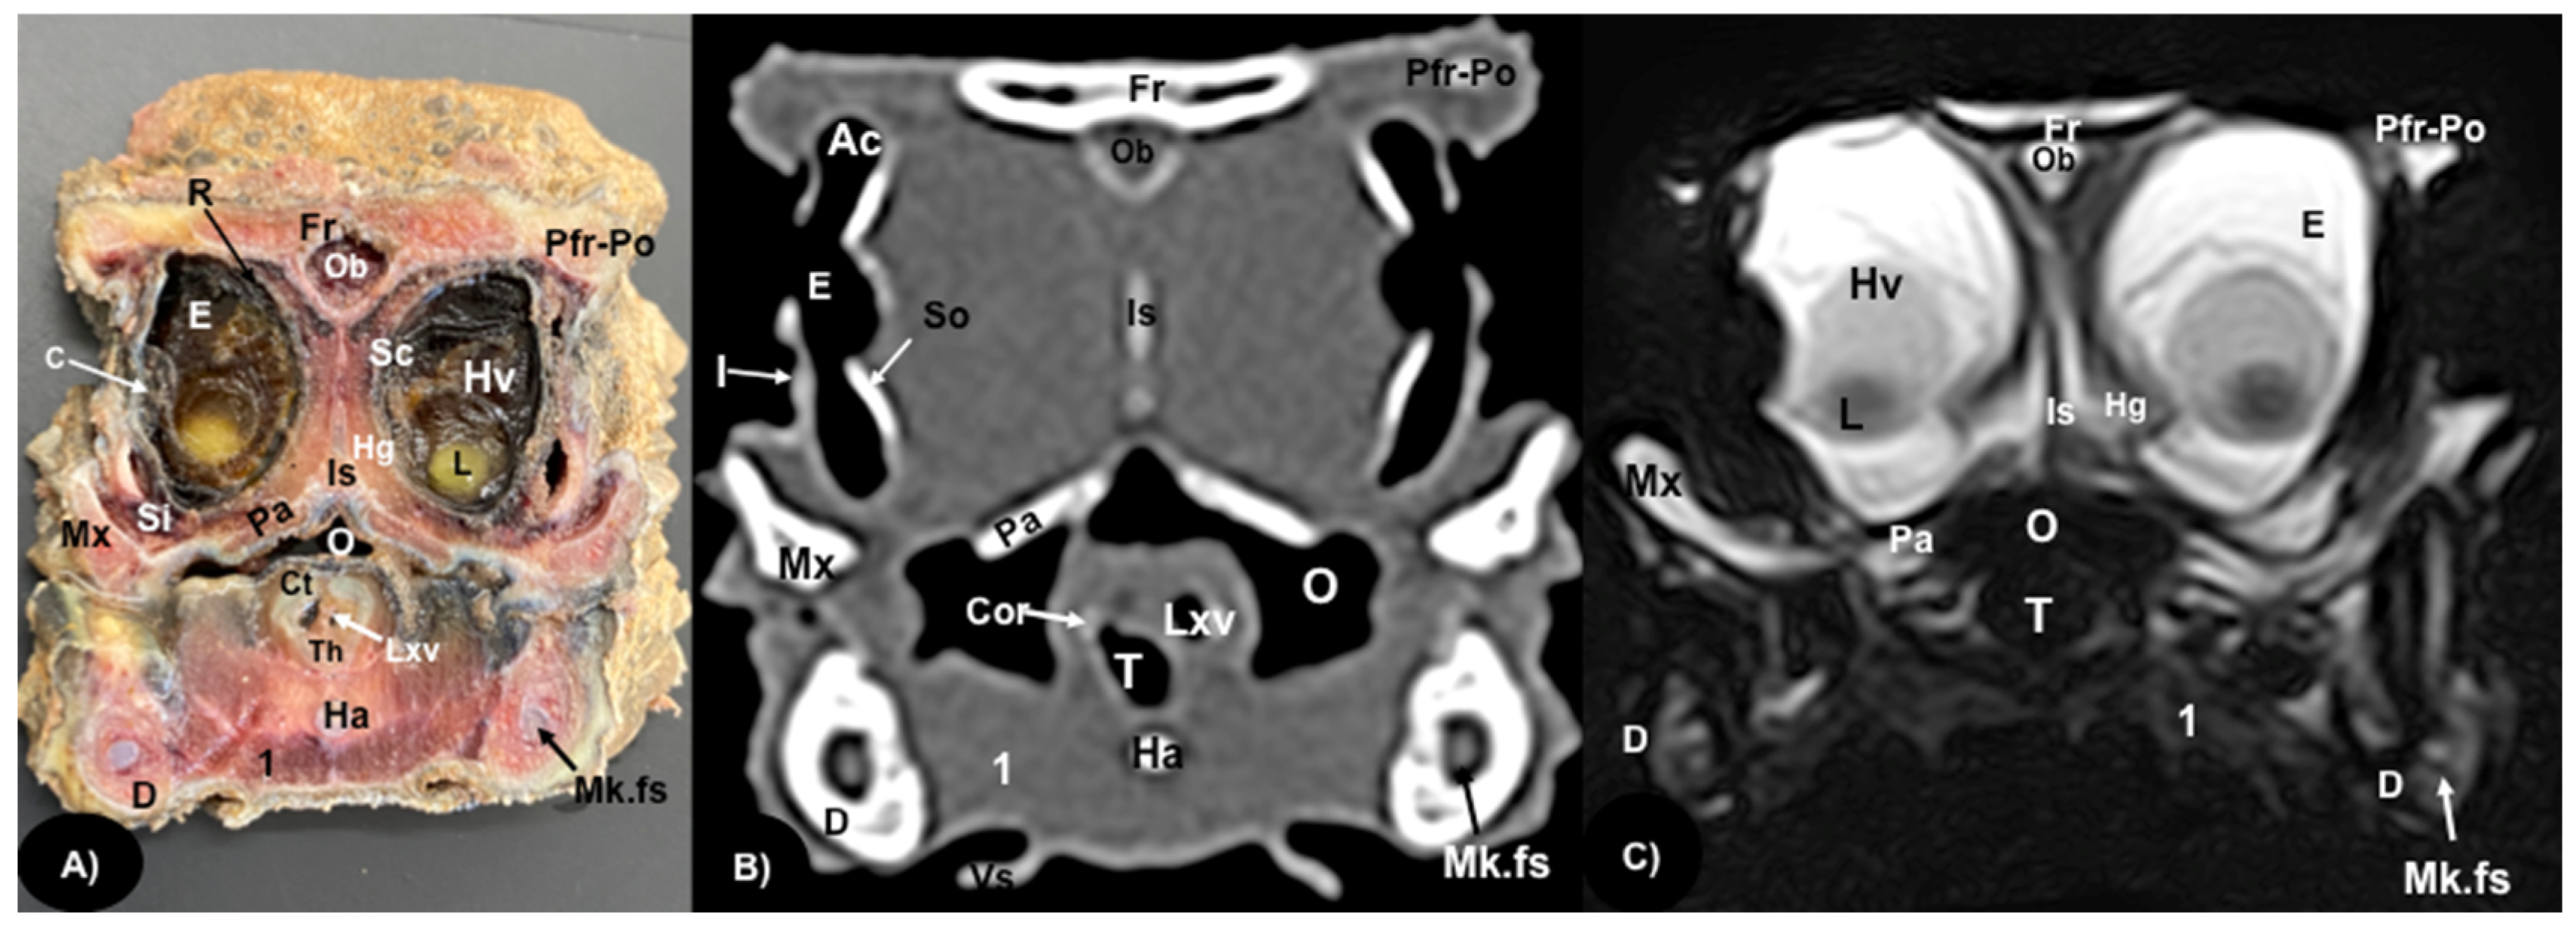

Figure 3.

Transversal gross-section (A), CT bone window (B), and MRI in T2W (C), images of the head of rhinoceros iguana in the orbital region corresponding to line II in Figure 1. Fr: Frontal bone. Pfr-Po: Postfrontal-postorbital bone. Ob: Olfactory bulb. Ac: Anterior chamber. R: Retina. So: Scleral ossicles. I: Iris. E: Eyeball. C: Cornea. Sc: Sclera. L: Lens. Hv: Vitreous chamber. Is: Interorbital septum. Hg: Harderian gland. Si: Infraorbital sinus. Pa: Palatine bone. Mx: Maxillary bone. O: Oral cavity. Cor: Corniculated tubercles of arytenoid cartilage. Lxv: Laryngeal ventricle. Th: Thyroid cartilage. D: Dentary bone. Mk.fs: Meckelian fossa. Ha: Hyoid apparatus. T: Trachea. 1: Musculus geniohyoideus + Musculus hyoglossus + Musculus intermandibularis. Vs: Ventral spines.

3.1. Anatomical Sections

3.2. Computed Tomography (CT)

Regarding the neurocranium, the CT images allowed us to distinguish bone structures such as the prefrontal, frontal, postfrontal-postorbital, parietal, squamosal, quadrate, epipterygoid, pterygoid, basioccipital, exoccipital, otoccipital and parabasisphenoid bones (Figure 3B, Figure 4B, Figure 5B and Figure 6B); related to the splanchnocranium, we observed the nasal, premaxilla, maxilla, septomaxilla, vomer, jugal and palatine bones, and the nasal septum (Figure 2B, Figure 3B, Figure 4B, Figure 7B and Figure 8B); the mandible structures such as the dentary, angular, surangular, coronoid and articular bones (Figure 2B, Figure 3B, Figure 4B, Figure 5B and Figure 6B) and the hyoid apparatus (Figure 2B, Figure 3B, Figure 4B, Figure 5B and Figure 6B). CT scanning and post-processing transverse images showed the relation between the different bones that form the head of the rhinoceros iguana, the junction of the nasal and the prefrontal bone, as well as that of the parietal bone with the postfrontal-postorbital bone (Figure 2B and Figure 4B), and the palatine and quadrate processes of pterygoid bone (Figure 5B and Figure 6B respectively). The prominent medial horn was identified dorsal to the nasal bone with soft-tissue attenuation and a thin, lamellar-shaped mineral structure bordering it regularly on its most external aspect (Figure 2B).

Concerning the nasal cavity, the transverse CT image showed the nasal glands as symmetrical bilateral structures, with regular and well-defined margins, located on both sides of the nasal cavity and with soft tissue attenuation (Figure 2B). Moreover, those structures with intraluminal gas content such as the nasal conchal recess (Figure 2B), oral cavity, nasopharyngeal duct, trachea, adductor fossa (Figure 4B) and the otic cavity (Figure 6B) were identified with this technique, appearing with a vacuum effect. In addition, there were areas of soft tissue attenuation medial to the mandible and bilateral to the hyoid apparatus, compatible with the intermandibularis, genihyioideus and hyoglossus muscles (1 in Figure 2B and Figure 3B), the pterygoideus, omohyoideus, sternohyoideus and ceratohyoideus muscles (2 in Figure 4B), the adductor mandibulae externus medialis and superficialis muscles located, respectively, dorsomedially and ventrolaterally to the adductor fossa (3 and 4 in Figure 4B and Figure 5B).

3.3. Magnetic Resonance Imaging (MRI)

The soft structures of the iguana’s head, such as the central nervous system as well as the eyeball’s structures (vitreous humor and lens), the oral cavity with the tongue and the masticatory muscles, showed an accurate visualization using MRI (Figure 2C, Figure 3C, Figure 4C, Figure 5C and Figure 6C). Therefore, an increased volume of both eyeballs in proportion to the size of the head was seen in all sequences (Figure 3C and Figure 7B). As in CT, the structures with gas content (Figure 2C and Figure 6C) appeared with a vacuum effect, being hypointense in all sequences. The nasal glands were bilaterally symmetric, with regular and well-defined margins, located on both sides of the nasal cavity, being iso/hyperintense in T1W and T2W sequences, compared to the encephalic grey matter (Figure 2C and Figure 4C). In contrast, the medial horn appeared hypo/isointense on T1W and T2W sequences concerning the white matter and with mild differentiation of the external bony cortex in relation to the white matter (Figure 2C).

In contrast to the CT images, the bone junctions were not distinguishable on MRI, but those bones that formed the neurocranium, such as the frontal, postfrontal-postorbitary, parietal and supraoccipital bones were identified (Figure 3C, Figure 4C, Figure 5C, Figure 6C and Figure 8B). The cranial musculature was found isointense concerning the thalamus in T2W. This technique enabled a better resolution to identify the muscle groups already mentioned (Figure 2C, Figure 3C, Figure 4C and Figure 5C). In the transverse planes of the encephalon, the cerebral cortex was observed slightly more hyperintense than the white matter, which was more hypointense in T2W sequences (Figure 4C). The diencephalic region (Figure 4C, Figure 5C and Figure 8B) was hypointense (T2W) compared to the cerebral cortex (Figure 5C), showing the thalamus and hypothalamus (Figure 8B). The brainstem appeared hypo/isointense in T2W compared to the cerebral cortex, as well as presenting a markedly tortuous horizontal alignment (Figure 8B). Moreover, the caudal colliculus and the fourth ventricle were also displayed in excellent detail. In the rostral aspect of the telencephalon, we distinguished the dorsal pallium rostral part with its lateral and medial portions (Figure 4C). Interestingly, the dorsal MRI image was quite helpful to identify the olfactory bulb located extracranially, which extended rostromedially between the eyeballs (Figure 3C, Figure 7B and Figure 8B).

Considering the green iguana [26], some differences were found between the bony structures of these species. Thus, we identified the presence of three horns on the dorsal aspect of the nasal region, which are absent in the green iguana. Moreover, the evaluation of the transverse CT images obtained in the bone window and the post-processing in MPR showed a lower prominence of the occipital ridge in the rhinoceros iguana compared to the green iguana. In addition, as described by other authors [22], the CT images of the rhinoceros iguana head displayed in excellent detail the bony structures compared to the anatomic gross-section. With MRI, the palatine, frontal, postfrontal-postorbital, parietal, supraoccipital bones and crest were distinguishable due to a gross-section and with both imaging techniques. In addition, the eyes were easily displayed with all the techniques used. Nonetheless, specific eyeball structures, such as the iris and the scleral ossifications, were better identified by CT and were hardly visible in anatomic gross-sections, where the lens, the retina, the sclera and the vitreous chamber could be visualized. Some of these structures are of scientific and morphological interest to perform further studies on the dimensions of the eyeball and vision ability [29,30].